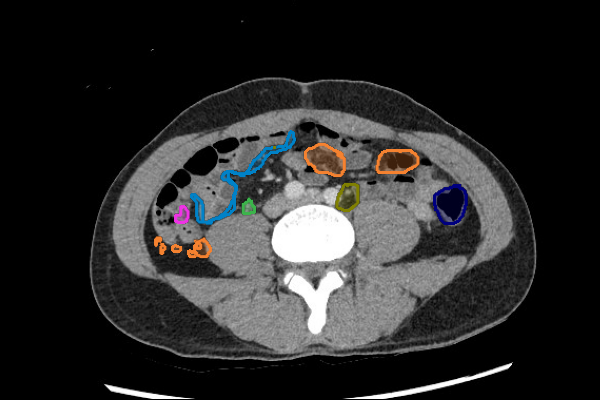

Legend

- Masses in the mesentery/peritoneum are often overlooked. Take advantage of multiplanar imaging and look in characteristic locations for peritoneal lesions.

- Look for filling defects in the vessels. Venous enlargement might indicate acute thrombus and confirming increased density by applying tight windows to potentially detect acute venous thrombus can be useful.